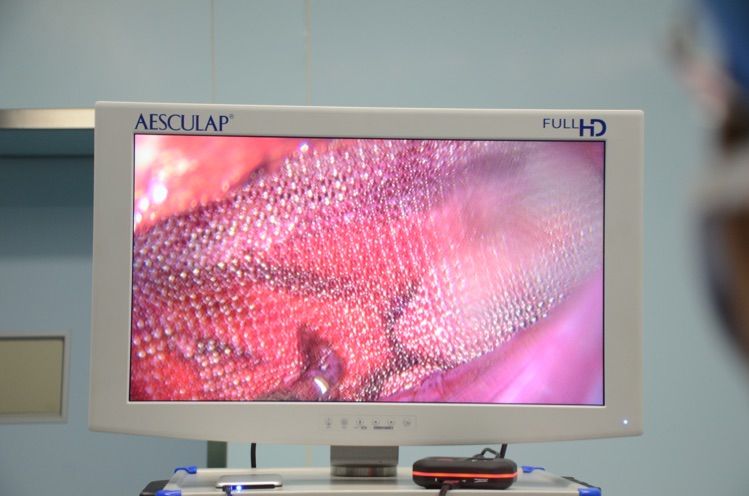

最後(hou),再來一(yi)例重(zhong)口味的(de),腹腔鏡下乙狀結腸異物(wù)取出術(shù)。患者酒後(hou)吞食三枚約10cm長(zhang)鐵釘,鐵釘随腸蠕動(dòng)逐漸下移,直至乙狀結腸,不能(néng)排(pai)出,出現(xian)穿孔傾向。急診手術(shù),選擇腹腔鏡探查,定位準确後(hou),切開乙狀結腸,順利取出所有(yǒu)鐵釘,再一(yi)期縫郃(he)乙狀結腸。術(shù)後(hou)患者恢複好,排(pai)氣(qi)早,無梗阻、無腸瘘表現(xian),患者滿意度很(hěn)高(gao)。